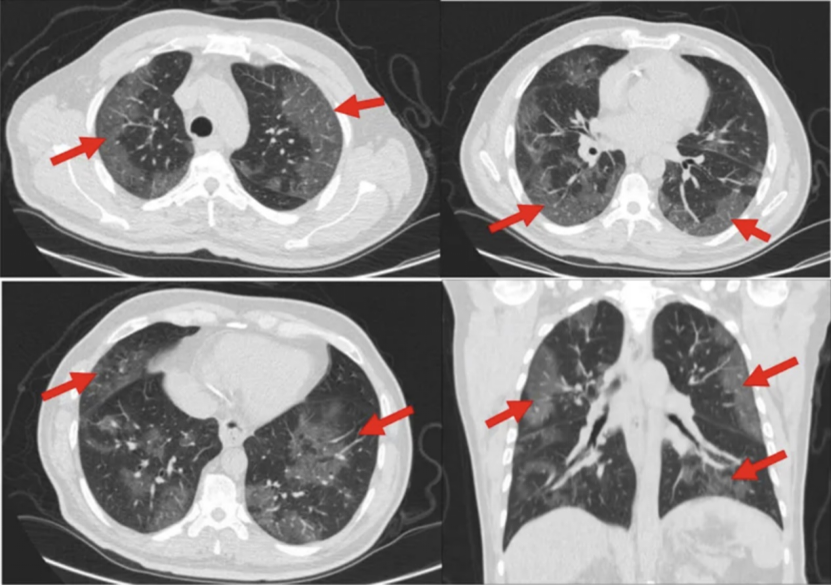

分叶、毛刺、胸膜牵拉

当肿瘤细胞越来越多,也越来越成熟时,肿瘤团块内部的细胞就会越来越趋向于向外侵袭发展,以获得额外的根据地。

在这个过程中,就会出现各种特异性的征象,比如:分叶(三叶草)、毛刺和胸膜牵拉。

所以,当我们看到一个非常成熟的实性病灶不仅在缓慢生长,还同时伴随以上几个特征,就真的需要小心,并考虑其恶性的可能性。

而与此同时,在肿瘤发生发展的过程中,尤其是在磨玻璃成分向实性成分演进的过程中,往往会在内部形成空泡、支气管充气等表现。

所以,当我们看到一个磨玻璃结节合并这样的 CT 描述,就需要引起警惕。